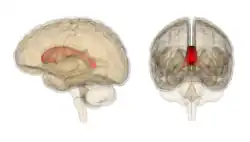

![]() Sagittal section of a brain, front part to the left. The corpus callosum can be seen in the center, in light gray | |

Corpus callosum with anatomography -